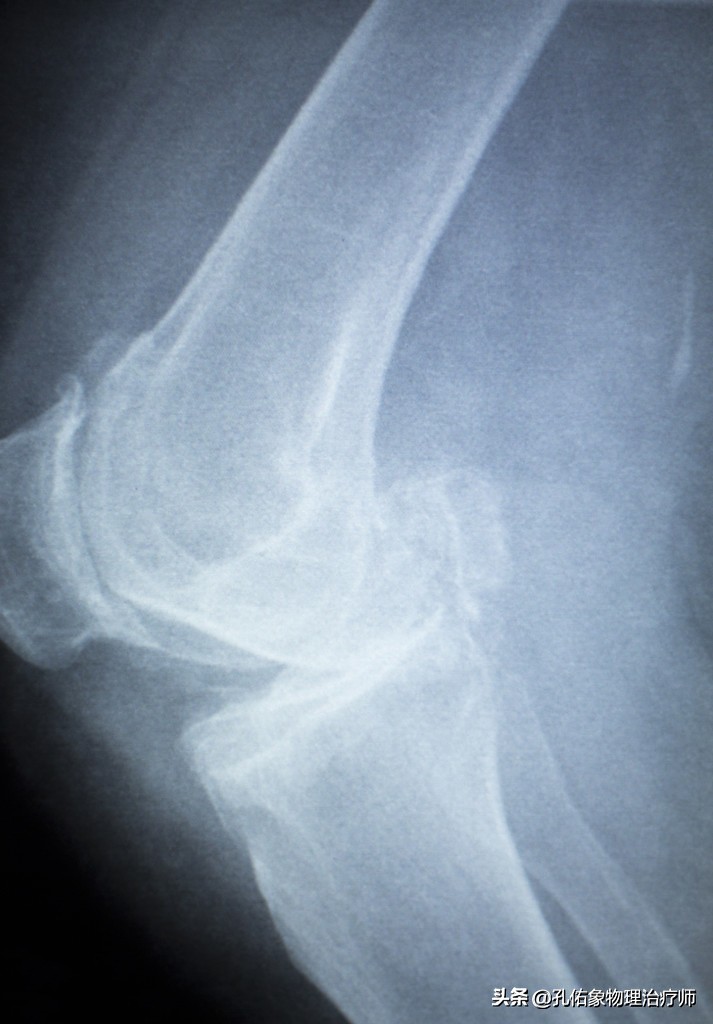

然而却忽略了半月板的问题,任其发展,继续忍受着疼痛做自己的事情,直到坚持不住了,没办法忍受疼痛时,才会来医院看膝关节究竟是怎么了?结果一拍片,就是下面这种状态。

膝关节是人体最复杂的关节,若是出现疼痛的话,不去深入找治病的因素,都笼统的通过拍片就诊断是膝关节骨性关节炎或是某某结构的损伤,那对于治疗而言,可想而知结局会是令人不满意的。